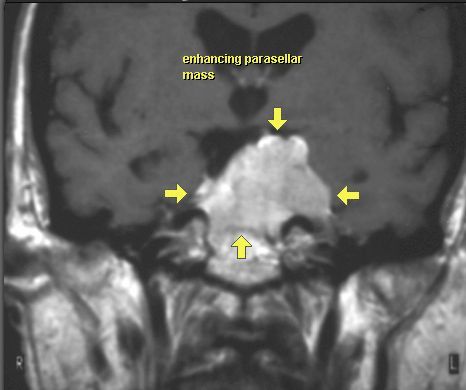

OPONIAK

MRI